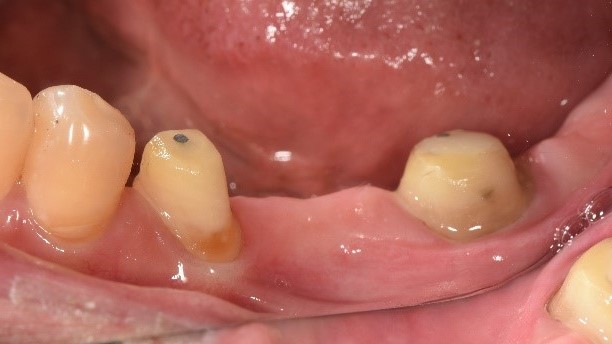

治療中:將牙齒修型、將鐵線拆除

治療後:復原完成,裝上牙橋